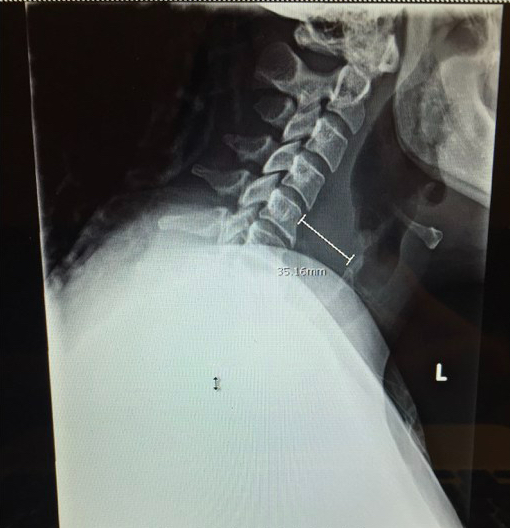

Lateral neck plain films can be used as a screening modality, particuluarly in children. A study performed by Nagy, which looked at 57 children ages 1-10 years old who had a high index of suspicion (i.e. only included patients with fever, limited neck range of motion, lateral neck mass, dysphagia and leukocyte count greater than 15,000 cells/mm3) for deep-neck infection, found latral neck plain films to have an 83% sensitivity. Widening of prevertebral space is consistent with a retropharyngeal abscess. In an adult, normal pervertebral space should be >6mm at C2 and >22mm at C6.

Figure 1: In this patient, the prevertebral space in front of C6 is 35 cm, which is greater than the normal prevertebral space of 22cm. This indicates soft tissue swelling consistent with a retropharyngeal abscess.